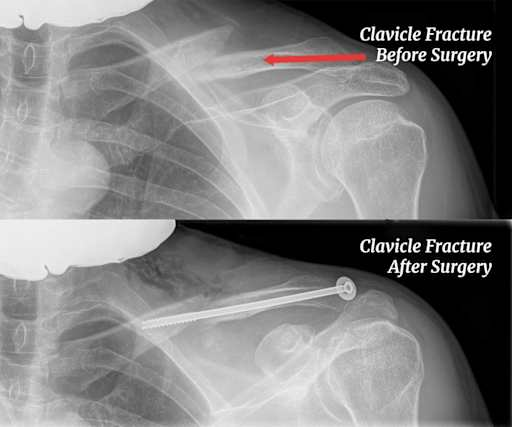

Clavicle fracture X-rays before and after surgery with plate and screw fixation

A fratura de clavícula é a lesão mais comum do ombro e uma das que mais aparecem nas emergências ortopédicas . Quando acontece, a dor é imediata e forte, e o paciente geralmente consegue apontar exatamente onde dói. A fratura pode ser simples, com o osso quebrando em duas partes, ou cominutiva, quando se fragmenta em vários pedaços.

Eu costumo explicar para meus pacientes que a clavícula é como uma vareta de madeira: se você aplica muita pressão no meio, ela quebra no ponto de menor resistência. No caso da clavícula, esse ponto costuma ser o terço médio, onde o osso é mais fino e tem menos suporte muscular. Cerca de 85% das fraturas acontecem nessa região .

Clavicle fracture X-rays before and after surgery with plate and screw fixation

Em fraturas menos desviadas, os sintomas podem ser mais brandos. O paciente sente dor ao mover o braço, mas consegue realizar algumas atividades. Isso pode dar a falsa impressão de que “não é nada grave” e levar a um atraso no diagnóstico. Meu conselho é: qualquer dor no ombro que apareça após uma queda ou impacto merece uma radiografia. Melhor pecar pelo excesso de cuidado do que lidar com uma complicação por descuido.

A radiografia simples é o primeiro exame solicitado e resolve a maioria dos casos . Ela mostra claramente o traço de fratura, o nível de deslocamento entre os fragmentos e a presença de fragmentos adicionais. Geralmente são pedidas duas incidências (anteroposterior e com inclinação cefálica) para uma visualização completa.

O tratamento cirúrgico para cada lesão também é diferente. Para a fratura, utilizam-se placas e parafusos para fixar os fragmentos. Para a luxação, utilizam-se técnicas de reconstrução ligamentar ou estabilização com sistemas de ancoragem como endobottons e fios de alta resistência. São cirurgias com abordagens e recuperações distintas.

A técnica mais utilizada para fraturas de clavícula é a fixação com placa e parafusos . Placas pré-moldadas, desenhadas especificamente para a anatomia da clavícula, são posicionadas sobre o osso para manter os fragmentos alinhados enquanto a consolidação acontece. Essas placas modernas oferecem alta estabilidade mecânica e permitem mobilização precoce do ombro.